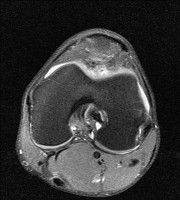

무릎 mri 간단히 봐주실 수 있으시나요 ㅠㅠ

안녕하세요 8년전 십자인대 수술하고 최근 무리한 운동에 무릎 불편감이 생겨서

mri 찍었습니다.

진단결과는 첫 찍은 병원에서 활액막염 이라는 진단을 받았습니다. 혹시 봐주실 수 있으실까요?

올라온 MRI가 단편적이라서 정확한 진단에 어려움이 있지만 십자인대에는 큰 이상이 있지는 않은것 같으며, 무릎관절내 물이 있는 것으로 보아 활액막염의 진단이 맞을 것 같습니다.

하지만 단편적인 영상이기 때문에 촬영병원에서 정확한 판독지 등을 받으시는 것이 좋겠습니다.